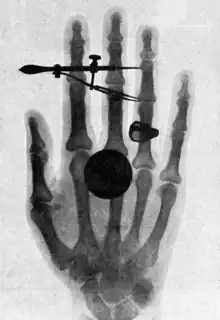

Wilhelm Conrad Röntgen (27 March 1845 – 10 February 1923) was a German physicist, who, on 8 November 1895, produced and detected electromagnetic radiation in a wavelength range today known as X-rays or Röntgen rays, an achievement that earned him the first Nobel Prize in Physics in 1901.

- I was working with a Crookes tube covered by a shield of black cardboard. A piece of barium platino-cyanide paper lay on the bench there. I had been passing a current through the tube, and I noticed a peculiar black line across the paper. … The effect was one which could only be produced, in ordinary parlance, by the passage of light. No light could come from the tube, because the shield which covered it was impervious to any light known, even that of the electric arc. … I did not think; I investigated. I assumed that the effect must have come from the tube, since its character indicated that it could come from nowhere else. I tested it. In a few minutes there was no doubt about it. Rays were coming from the tube which had a luminescent effect upon the paper. I tried it successfully at greater and greater distances, even at two metres. It seemed at first a new kind of invisible light. It was clearly something new, something unrecorded.

- Having discovered the existence of a new kind of rays, I of course began to investigate what they would do. … It soon appeared from tests that the rays had penetrative power to a degree hitherto unknown. They penetrated paper, wood, and cloth with ease; and the thickness of the substance made no perceptible difference, within reasonable limits. … The rays passed through all the metals tested, with a facility varying, roughly speaking, with the density of the metal. These phenomena I have discussed carefully in my report to the Würzburg society, and you will find all the technical results therein stated.